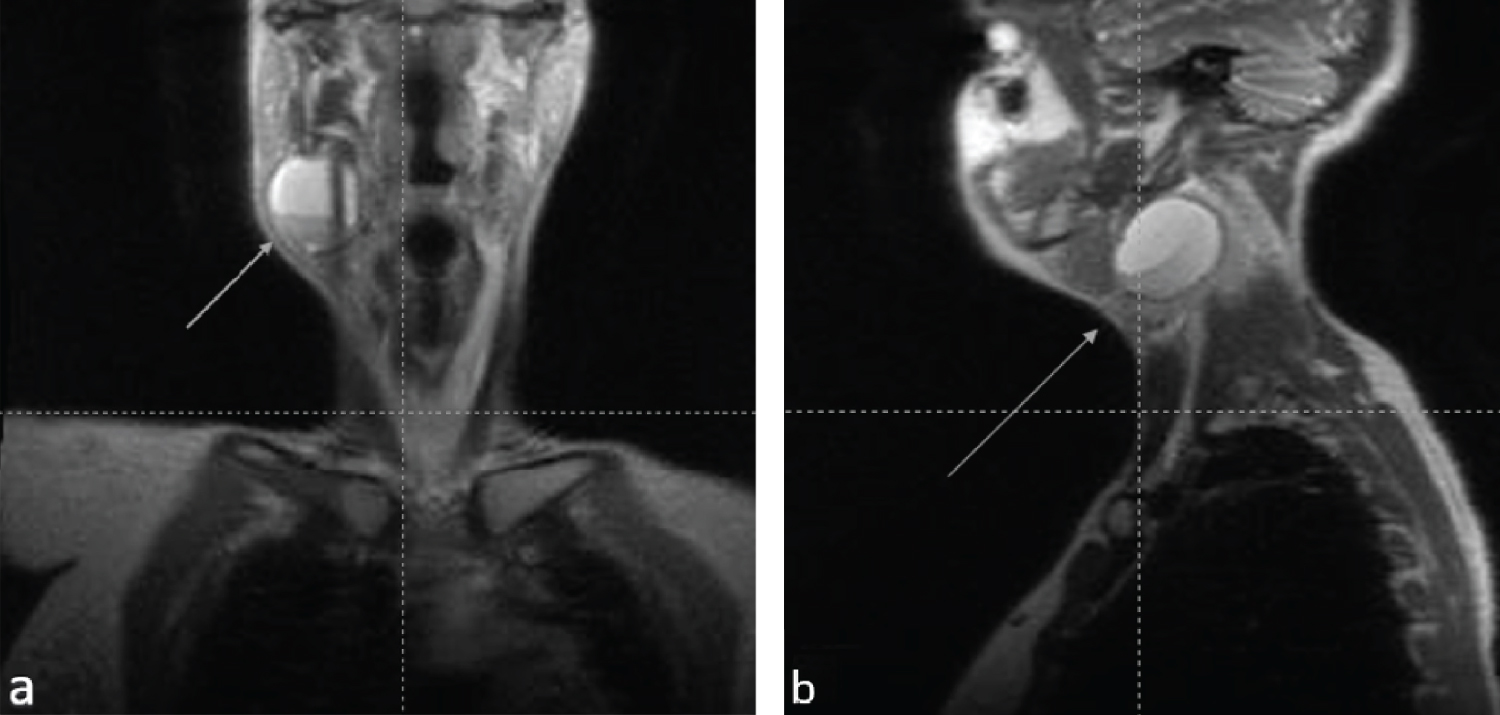

We report on a healthy 30-year-old pregnant woman who presented a right sided tense-elastic neck swelling, starting from the seventh month of pregnancy (Figure 1). The ultrasound examination demonstrated a 41 × 20 mm oval cystic formation characterized by corpuscular content, localized at right mandibular angle in a space between the submandibular and parotid gland. The formation shows no vascular enhancement at Doppler sampling, being compatible with a branchial cleft cyst arisen from the second cleft. Nearby structures were deemed normal, no lymphadenopathy was detected (Figure 2). An iterative clinical and ultrasound check demonstrated its progressive growth, reaching maximum expansion at delivery. The cyst did not cause any pain or functional impairment. MRI examination of the neck, conducted after delivery, confirmed the known cyst, 38 × 40 × 48 mm in size with an oval morphology and clear limits, without infiltrating characteristics, with a finely structured proteinaceous sedimentation, located at right lateral neck compartment, antero-medial to the sternocleidomastoid muscle. No significant loco-regional adenopathies were documented, the adipose layers were preserved, and the parotid and submandibular glands were free from focal alterations. These findings were compatible with Bailey type II second branchial cleft cysts [4,5,9,10] (Figure 3). After delivery, the cyst remained stable for about four months and then gradually shrunk within a month. Subsequently surgical excision was performed. The surgical material was sent for histological examination, which confirmed the diagnosis of second branchial cleft cyst and detected the positivity at immunohistochemistry for ER on the lining epithelium using anti-ERα (SP1) antibodies (Figure 4).

Figure 3: MRI images of the neck confirmed the cyst (white arrow), 38 × 40 × 48 mm in size with a rounded neat shape, with no infiltration, located at right lateral neck compartment, antero-medial to the sternocleidomastoid muscle as shown in (A) Coronal view and (B) Sagittal view. View Figure 3